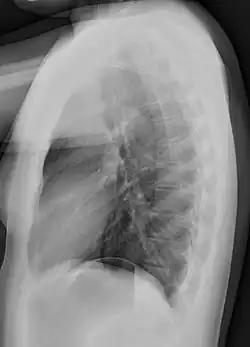

Different views (also known as projections) of the chest can be obtained by changing the relative orientation of the body and the direction of the x-ray beam. The most common views are posteroanterior, anteroposterior, and lateral. In a posteroanterior (PA) view, the x-ray source is positioned so that the x-ray beam enters through the posterior (back) aspect of the chest and exits out of the anterior (front) aspect, where the beam is detected. To obtain this view, the patient stands facing a flat surface behind which is an x-ray detector. A radiation source is positioned behind the patient at a standard distance (most often 6 feet, 1,8m), and the x-ray beam is fired toward the patient.

In anteroposterior (AP) views, the positions of the x-ray source and detector are reversed: the x-ray beam enters through the anterior aspect and exits through the posterior aspect of the chest. AP chest x-rays are harder to read than PA x-rays and are therefore generally reserved for situations where it is difficult for the patient to get an ordinary chest x-ray, such as when the patient is bedridden. In this situation, mobile X-ray equipment is used to obtain a lying down chest x-ray (known as a "supine film"). As a result, most supine films are also AP.

Lateral views of the chest are obtained in a similar fashion as the posteroanterior views, except in the lateral view, the patient stands with both arms raised and the left side of the chest pressed against a flat surface.

Typical views

Required projections can vary by country and hospital, although an erect posteroanterior (PA) projection is typically the first preference. If this is not possible, then an anteroposterior view will be taken. Further imaging depends on local protocols which is dependent on the hospital protocols, the availability of other imaging modalities and the preference of the image interpreter. In the UK, the standard chest radiography protocol is to take an erect posteroanterior view only and a lateral one only on request by a radiologist.[5] In the US, chest radiography includes a PA and Lateral with the patient standing or sitting up. Special projections include an AP in cases where the image needs to be obtained stat (immediately) and with a portable device, particularly when a patient cannot be safely positioned upright. Lateral decubitus may be used for visualization of air-fluid levels if an upright image cannot be obtained. Anteroposterior (AP) Axial Lordotic projects the clavicles above the lung fields, allowing better visualization of the apices (which is extremely useful when looking for evidence of primary tuberculosis).